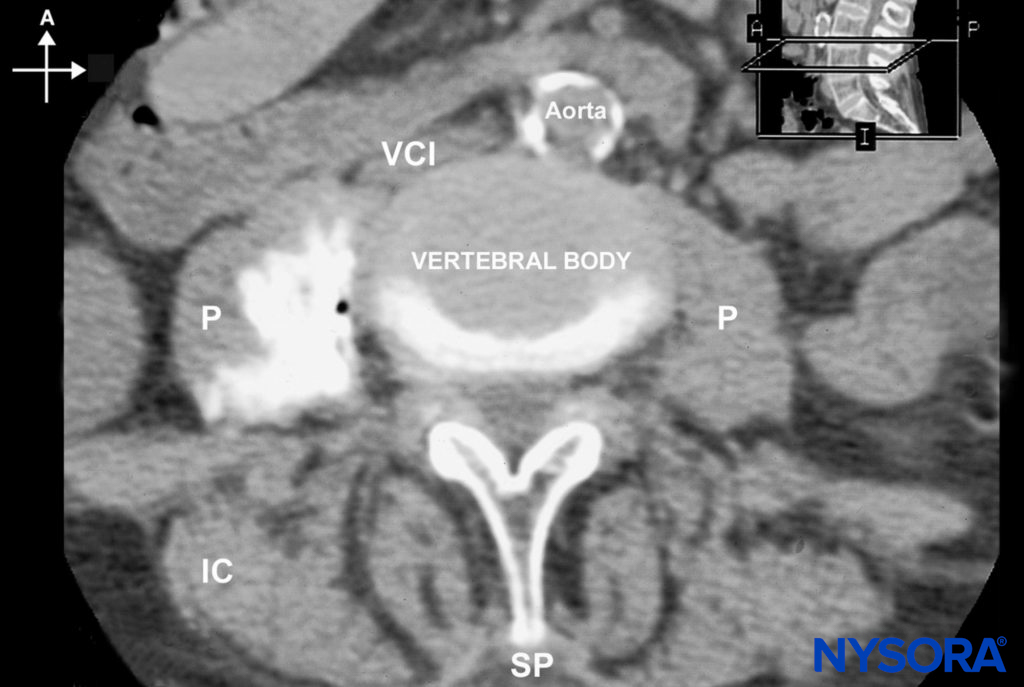

Continuous infusion is initiated after an initial bolus of dilute local anesthetic through the catheter. For this purpose, we routinely use ropivacaine 0.2% (15–20 mL). The infusion is maintained at 10 mL/h or 5 mL/h when a patient-controlled analgesia (PCA) dose is planned (5 mL/q60min). Figures 7 and 8 show the dispersion of 20 mL of a contrast solution within the psoas sheath.

FIGURE 8. An MRI image demonstrating the distribution of local anesthetic after lumbar plexus block. (A, anterior; I, inferior; IC, iliac crest; P, psoas muscle; SP, spinous process; VCI, vena cava inferior.)